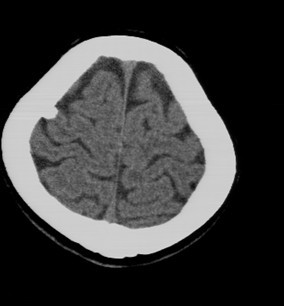

后枕部疼痛来检查的,无任何相关病史

骨瘤吧?

考虑脑膜钙化或小脑膜瘤钙化。

钙化

考虑骨瘤或小脑膜瘤钙化。

脑沟内钙化灶,考虑陈旧性脑膜感染

钙化灶。

钙化灶

考虑脑膜钙化

小脑膜瘤钙化

良性钙斑

考虑脑膜钙化或小脑膜瘤钙化